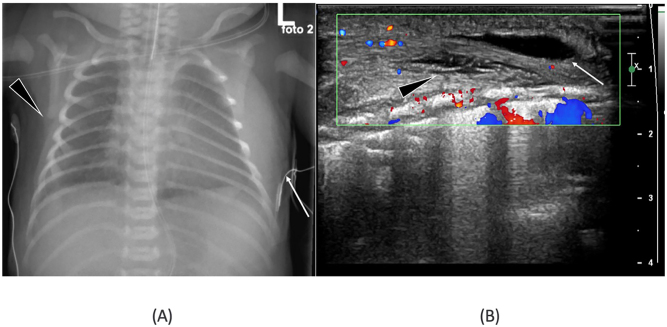

Case presentation: A 32 weeks 6 days pregnant Caucasian woman was admitted after premature prelabor rupture of membranes (PPROM). Fetal ultrasound showed no abnormalities, the infant was born by a caesarean section. The delivery was complicated by the infant's transverse position. A female infant was born with a large left-sided dorsal soft tissue mass at the thoracic level with elastic consistency, and multiple skin lacerations. A broad differential diagnosis was made. Additional imaging was suggestive for a posttraumatic swelling due to transverse position during birth. The mass decreased and disappeared over three days.